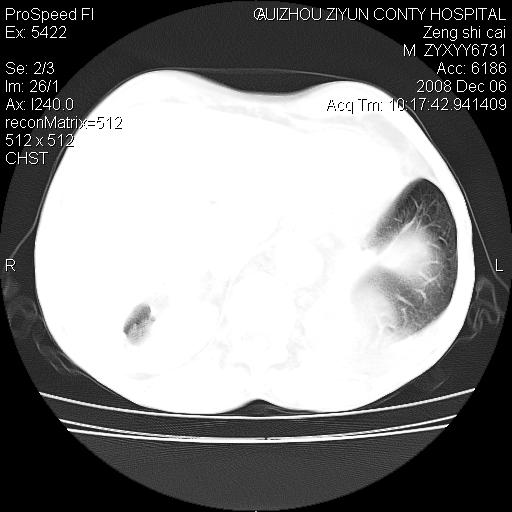

标题: CT16961:M、71岁,咳嗽半年,无血痰;胸片示右肺占位。 [打印本页]

标题: CT16961:M、71岁,咳嗽半年,无血痰;胸片示右肺占位。

右肺纵隔型肺癌伴纵隔淋巴结及胸膜转移!

右肺纵隔型肺癌伴纵隔淋巴结转移!双侧胸水!

1)考虑右肺上叶纵隔型肺癌伴纵隔淋巴结转移。2)心包积液,双侧胸腔积液。

右肺癌并纵隔淋巴转移,腹膜后转移可能性大,两侧胸腔积液

右肺上叶纵隔型肺癌伴纵隔淋巴结转移。心包积液,双侧胸腔积液。

右肺纵隔型肺癌伴纵隔淋巴结转移!双侧胸水\\心包积液

建议强化!主要鉴别是淋巴瘤与肺癌淋巴结转移。

右肺纵隔型肺癌伴纵隔淋巴结及胸膜转移